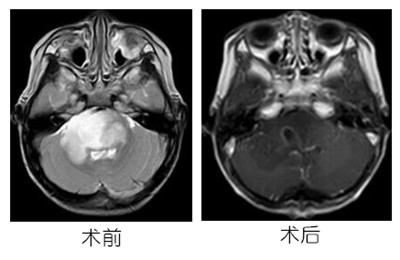

患儿赖某某,男,4岁7月,因“发现双脚步态异常1年余”入院。患儿缘于一年余前无明显诱因出现双脚步态异常,主要表现为步行时双脚后跟踮起。辅助检查:外院颅脑MRI提示脑干占位性病变,考虑胶质瘤可能性大。

入院后完善术前检查,广东三九脑科医院小儿神经外科全麻下为其进行“后正中开颅脑干占位性病变切除术”。术中显微镜下部分切除桥脑区肿瘤,过程中曾出现心律下降、呼吸节律改变,但逐渐恢复。术中后组颅神经及重要血管均予解剖保留完整。术后患儿继续辅以放化疗治疗。病理诊断:弥漫性星形细胞,IDH突变型,WHO II级。

手术治疗是目前治疗主要手段,本例病人肿瘤累及脑干,术中曾出现心律下降、呼吸节律改变,可见手术的精细操作对于患儿生命及一个家庭是多么重要。术后围手术期的生命体征监测及积极的对症用药也显得尤为重要。该患儿术后复查提示后颅窝水肿明显,颅内压监测提示颅内压力高,给予脱水、激素等治疗后逐渐下降。